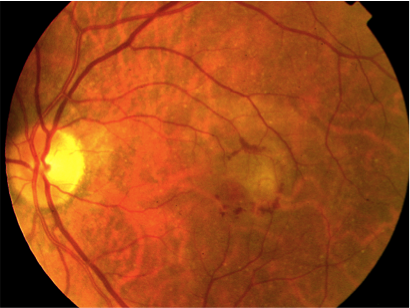

DMAE exudativa o húmeda